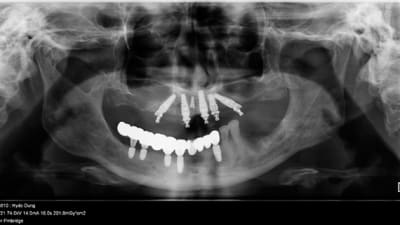

Case Report Treatment of a Maxillary Arch Featuring NobelProcera Zirconia Implant Bridge Dennis Nagata, DDS, James Michino, DMD July 15, 2021 2 min read